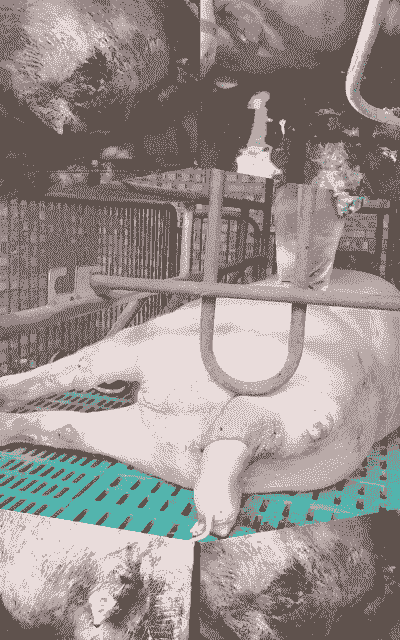

母猪产后冲洗子宫是一种常见的护理措施,旨在清除子宫内的残留物和炎性分泌物,预防感染和促进子宫恢复。以下是冲洗子宫的详细步骤和注意事项:

使用容量约6000-8000毫升的干净容器,下接1米左右可消毒软管,再接球型精液注入管。

注入清洗管

将清洗管插入阴道内约7.5-10厘米,暂停使清洗水逆流而出,直至不含杂质。

深入清洗

继续插入清洗管约10-15厘米,暂停使流出的清洗水无杂质。